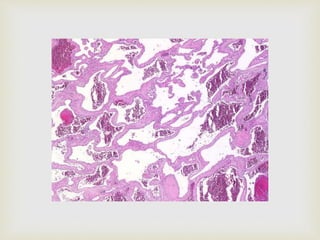

 Nodular mass of fibrous connective tissue covered with

stratified squamous epithelium

 Non-encapsulated lesion; fibrous tissue blends into the

surrounding connective tissue

 CONNECTIVE TISSUE

 Dense and collagenized; scattered inflammation

 Collagen fibres are arranged in radiating, circular or

haphazard pattern

 EPITHELIUM

 Atrophy;flat rete ridges or thin and elongated rete

ridges

 Sometimes hyperkeratosis (clinically white)

FIBROMA

Histopathology